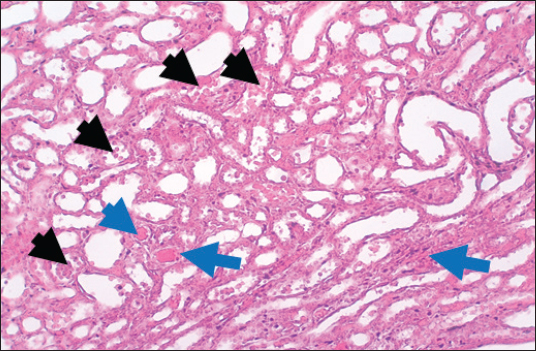

In the control group, histological analysis of kidney sections revealed intact glomeruli and renal tubules (Fig. 1). Conversely, Figure 2 presents a kidney section from the green tea group, which exhibited normal renal tubular epithelial cells, a well-preserved tubular lumen, and an overall normal tubular texture, although some glomeruli showed mild atrophy. The renal section of gentamicin showed atrophy of the glomerular tuft, expansion of the globular space, and significant hyperemia lesions in some glomeruli associated with substantial damage to the superficial cell layer (epithelial cells) in the proximal renal tubules, resulting in a reduction of the tubular lumen space (Fig. 3). In contrast, kidney sections from the gentamicin group that received green tea treatment revealed a marked reveal of both glomeruli and renal tubular epithelium, which appeared normal (Fig. 4 and Fig. 5).

Fig. 4. Kidney of treatment group. The section shows severe hemorrhage (RBCS accumulation in the proximal renal tubules, Black arrows) with ahyperemic lesion in the section of renal tubules (Blue arrows).H and E (10X).

Fig. 5. Kidney of protective group. The section shows normal renal tubular epithelial cells with a normal tubular lumen (Black arrows). A normal tubular texture with mild atrophy can be seen in some glomeruli (Blue arrow). H and E (10X).